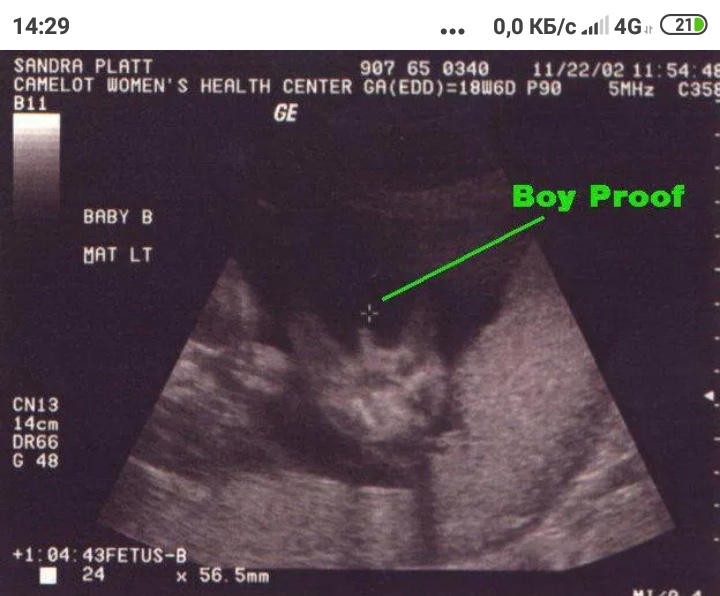

Особенности УЗИ при определении пола ребенка

Раздел: Идеи и советы